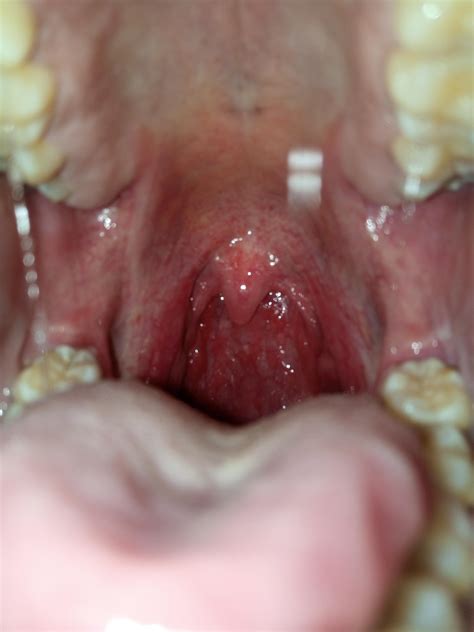

If you have ever peered into a mirror, opened your mouth wide, and noticed a strange, bumpy appearance at the back of your throat, you might have felt a wave of immediate concern. Many people often search for Cobblestone Throat Pictures online to compare their own symptoms with what they see on screen. This textured, grainy appearance—often resembling an old cobblestone street—is a common clinical sign that your body is dealing with some form of chronic irritation or inflammation. While the appearance can look alarming, it is usually a symptom of an underlying condition rather than a disease in itself.

The term "cobblestone throat" refers to the physical changes that occur in the lymphoid tissue located on the back wall of the throat, medically known as the pharynx. Under normal circumstances, the tissue in the back of your throat should look relatively smooth, even if it is slightly pink. When the throat is constantly exposed to irritants, the lymph nodes (part of your immune system) become enlarged and inflamed.

This inflammation creates the characteristic raised, irregular, and bumpy texture that triggers people to look up Cobblestone Throat Pictures. It is essentially your immune system’s way of saying, "I am fighting something off." Because the pharynx is a primary gateway for air and food, it is susceptible to a variety of environmental and biological triggers that lead to this specific appearance.